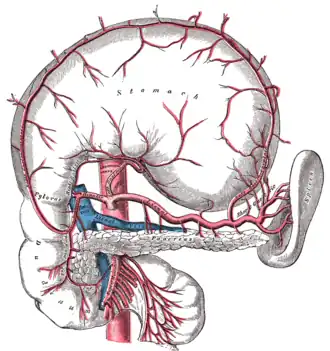

Le tronc cœliaque et ses branches.

Vascularisation et innervation

La vascularisation artérielle de la rate se fait principalement par l'artère splénique (artère liénale). Celle-ci étant l'une des 3 branches du tronc cœliaque qui naît de l'aorte au niveau de la 12e vertèbre thoracique. Après un trajet très sinueux sur le bord supérieur du pancréas, elle pénètre dans le parenchyme par le hile en se divisant en deux branches supérieure et inférieure ; ceci explique l'existence de la splénectomie partielle. Ensuite ces branches se divisent en artères trabéculaires qui cheminent dans les travées conjonctives. Elles-mêmes donnent les artères centrales en sortant de la travée, qui s'entourent d'un manchon de pulpe blanche (surtout lymphocytes T). L'artère centrale se poursuit et sort de la pulpe blanche pour donner des plus petites branches : les « artères pénicillées ». Celles-ci se finissent par des capillaires avec des sortes de bouchons qui entourent leur terminaison : ce sont les capillaires à housse. Ces capillaires terminaux sont obturés et il va y avoir des passages entre les cellules endothéliales terminales, et le sang va sortir des vaisseaux et traverser le parenchyme splénique pour rejoindre les sinus veineux. On a donc une circulation fermée et une circulation ouverte.

La vascularisation veineuse se fait quant à elle par la veine splénique (veine liénale), qui rentre dans la constitution du tronc porte avec les veines mésentériques supérieure et inférieure.